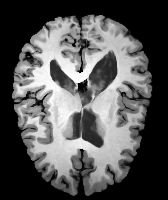

Results: All trained networks are evaluated using Dice overlap scores between predictions and the manual segmentations for the segmentation network, or between the warped moving segmentations and the target segmentations for the registration network. Tabs. 1 and 2 show results for the knee and brain MRI experiments respectively in Dice scores (%). Fig. 2 shows examples of knee MRI registrations and brain MRI segmentations.

Qualitative results: DA achieves more anatomically consistent registrations than the mono-networks on the knee (Fig. 2) and Brain MRI samples (see supplementary material).